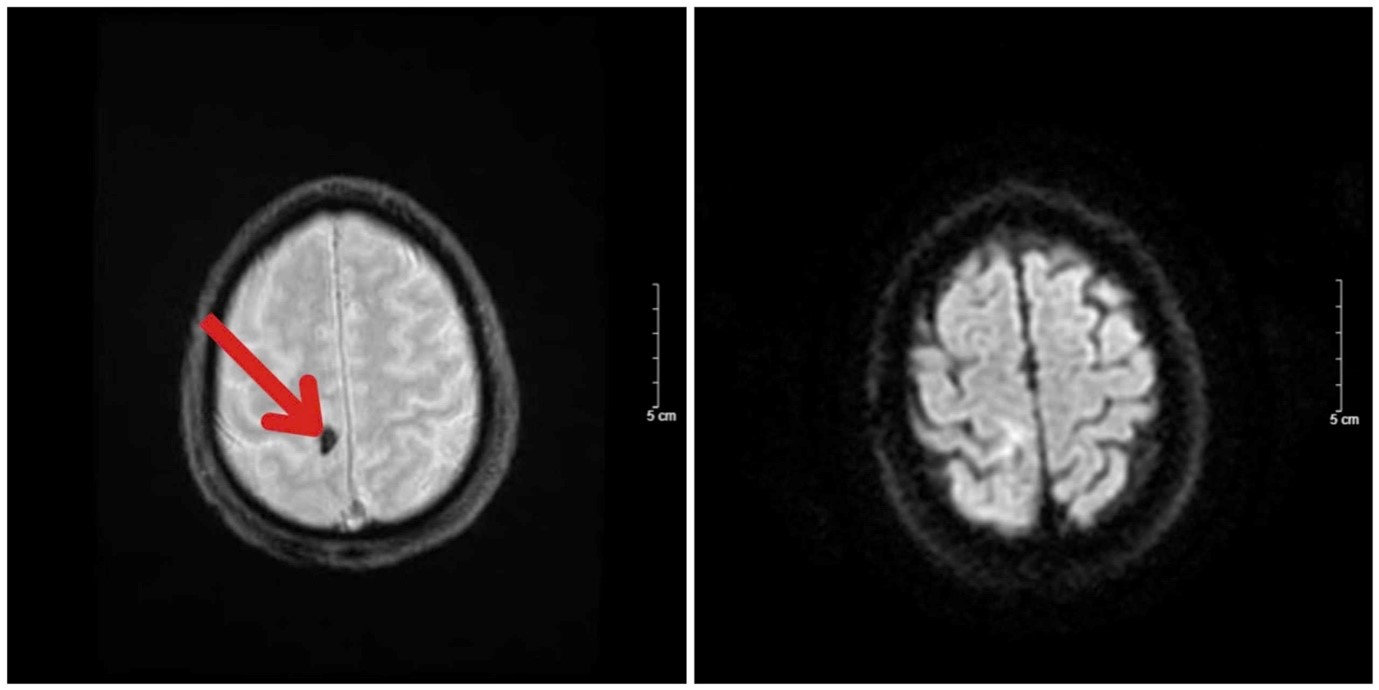

So sánh hình ảnh cộng hưởng từ sọ não trước điều trị và sau 4 tháng điều trị

Kết quả hình ảnh chụp cộng hưởng từ sọ não sau 4 tháng điều trị: Khối u thuỳ trán phải kích thước 8x10mm (giảm hơn 70% kích thước so với trước điều trị), không phát hiện tổn thương mới.

Hình 3. Hình ảnh chụp cộng hưởng từ sọ não sau điều trị: Khối u thuỳ trán phải (mũi tên đỏ) kích thước 8x10mm, ngấm thuốc dạng viền sau tiêm kèm phù não xung quanh

Hình 4. So sánh hình ảnh chụp cộng hưởng từ sọ não trước và sau điều trị xạ phẫu bằng dao gamma và điều trị toàn thân

A. Hình ảnh chụp cộng hưởng từ sọ não trên chuỗi xung FLAIR: Khối u thuỳ trán phải giảm kích thước từ 18x18mm xuống còn 8x10mm

B. Hình ảnh chụp cộng hưởng từ sọ não trên chuỗi xung T2: Khối u não ở thuỳ trán phải giảm kích thước sau điều trị